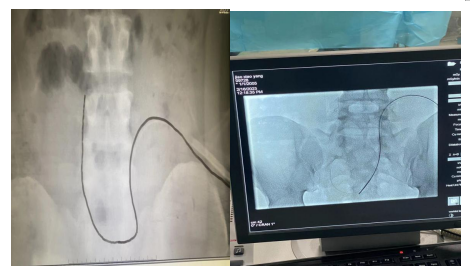

腹膜透析管复位影像

患者家属因考虑近期移植不愿给孩子做二次手术,遂至麦田影院 住院。住院期间麦田影院 儿童紫癜肾病诊疗中心翟文生主任、宋纯东主任、郭庆寅副主任带领儿科腹膜透析团队制定了明确腹透导管位置,判断导管有无阻塞,分析病因寻找解决方法的“三步走”方案。患者首先至放射科行立位腹平片检查明确腹膜透析导管位置,然后由超声科张小东副主任医师行彩超探查排除大网膜包裹、腹膜透析导管腹内段通畅无阻塞。排除手术禁忌证后由儿童紫癜肾病诊疗中心段凤阳医生与介入科吴涛主任制定手术方案,在DSA引导下,介入科医生苗牛采用多功能导管联合加硬导丝对腹透管漂管进行复位,术后患者腹透管恢复至盆腔内,出入液通畅,功能恢复。

腹膜透析是治疗急慢性肾功能衰竭的重要手段,透析导管漂管移位导致导管功能不良的常见并发症,一旦出现通常影响腹膜透析疗效和患者生活质量。针对腹膜透析导管漂管的处理,运动通便、手法复位等非手术方式通畅效果有限,而效果较好的开腹或腹腔镜直视下复位对患者影响较大,DSA引导下介入治疗腹透管漂管是一种全新的复位方法,创意新颖,高效安全,费用低。适应症:1、腹膜透析漂管患者;2、无大网膜包裹及透析管内阻塞;3、运动及手法复位等常规操作效果不佳患者。